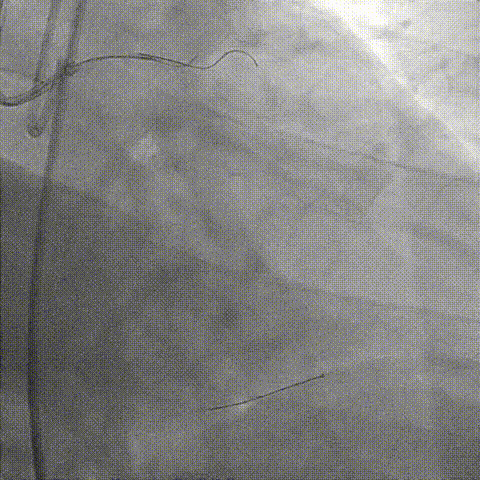

LAD开口全闭、OM开口70%

LM未见狭窄、LCX近中段40-50%狭窄

RCA 近段 60%、中段重度迂曲